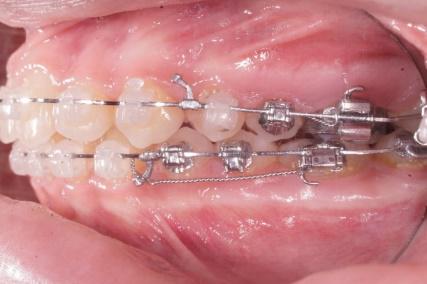

Bagues en céramiques

Les bagues sont maintenant auto-ligaturantes et en céramique